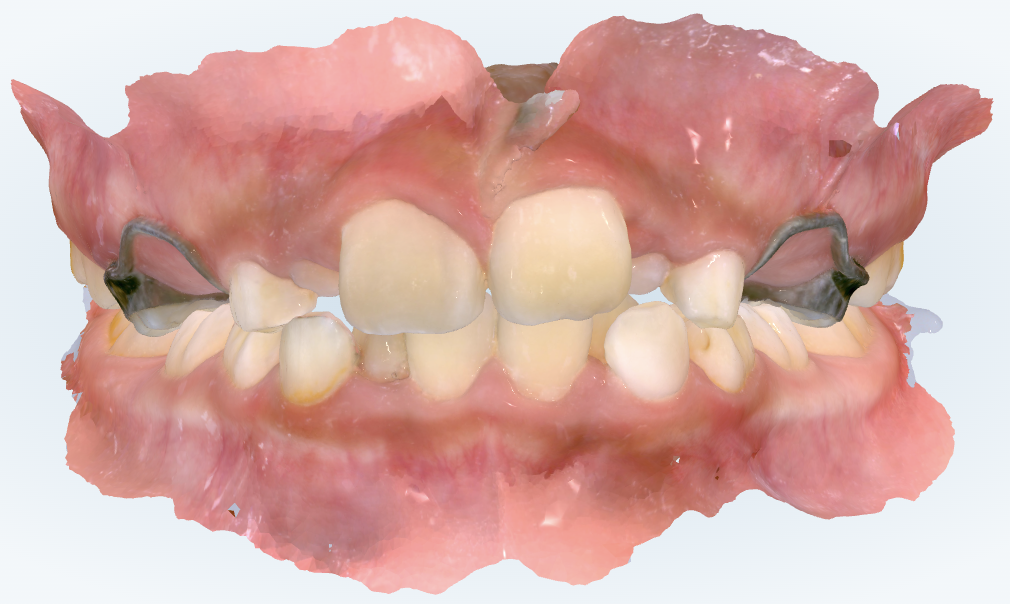

初診時の画像診断

上下の歯並びに大きなガタガタがありました。

上の歯並びにはガタガタの悪化を防ぐ目的でバンドループが装着されていました。